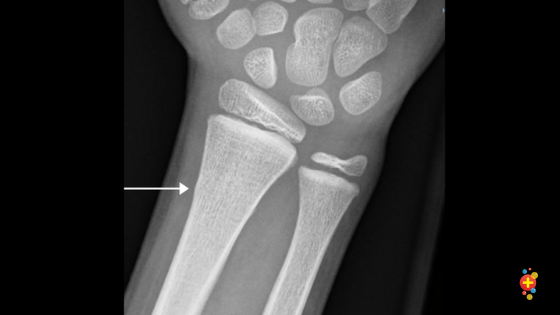

Two hours and three x-rays later, the doctor confirmed it. I don’t even remember touching the ground with my hand at all, but I must have tried to catch myself because I cracked my radius clean through just over an inch above my wrist. It was fully broken, but it never shifted out of alignment because it had also impacted into itself.

And here’s mine:

Clean, but unusable.